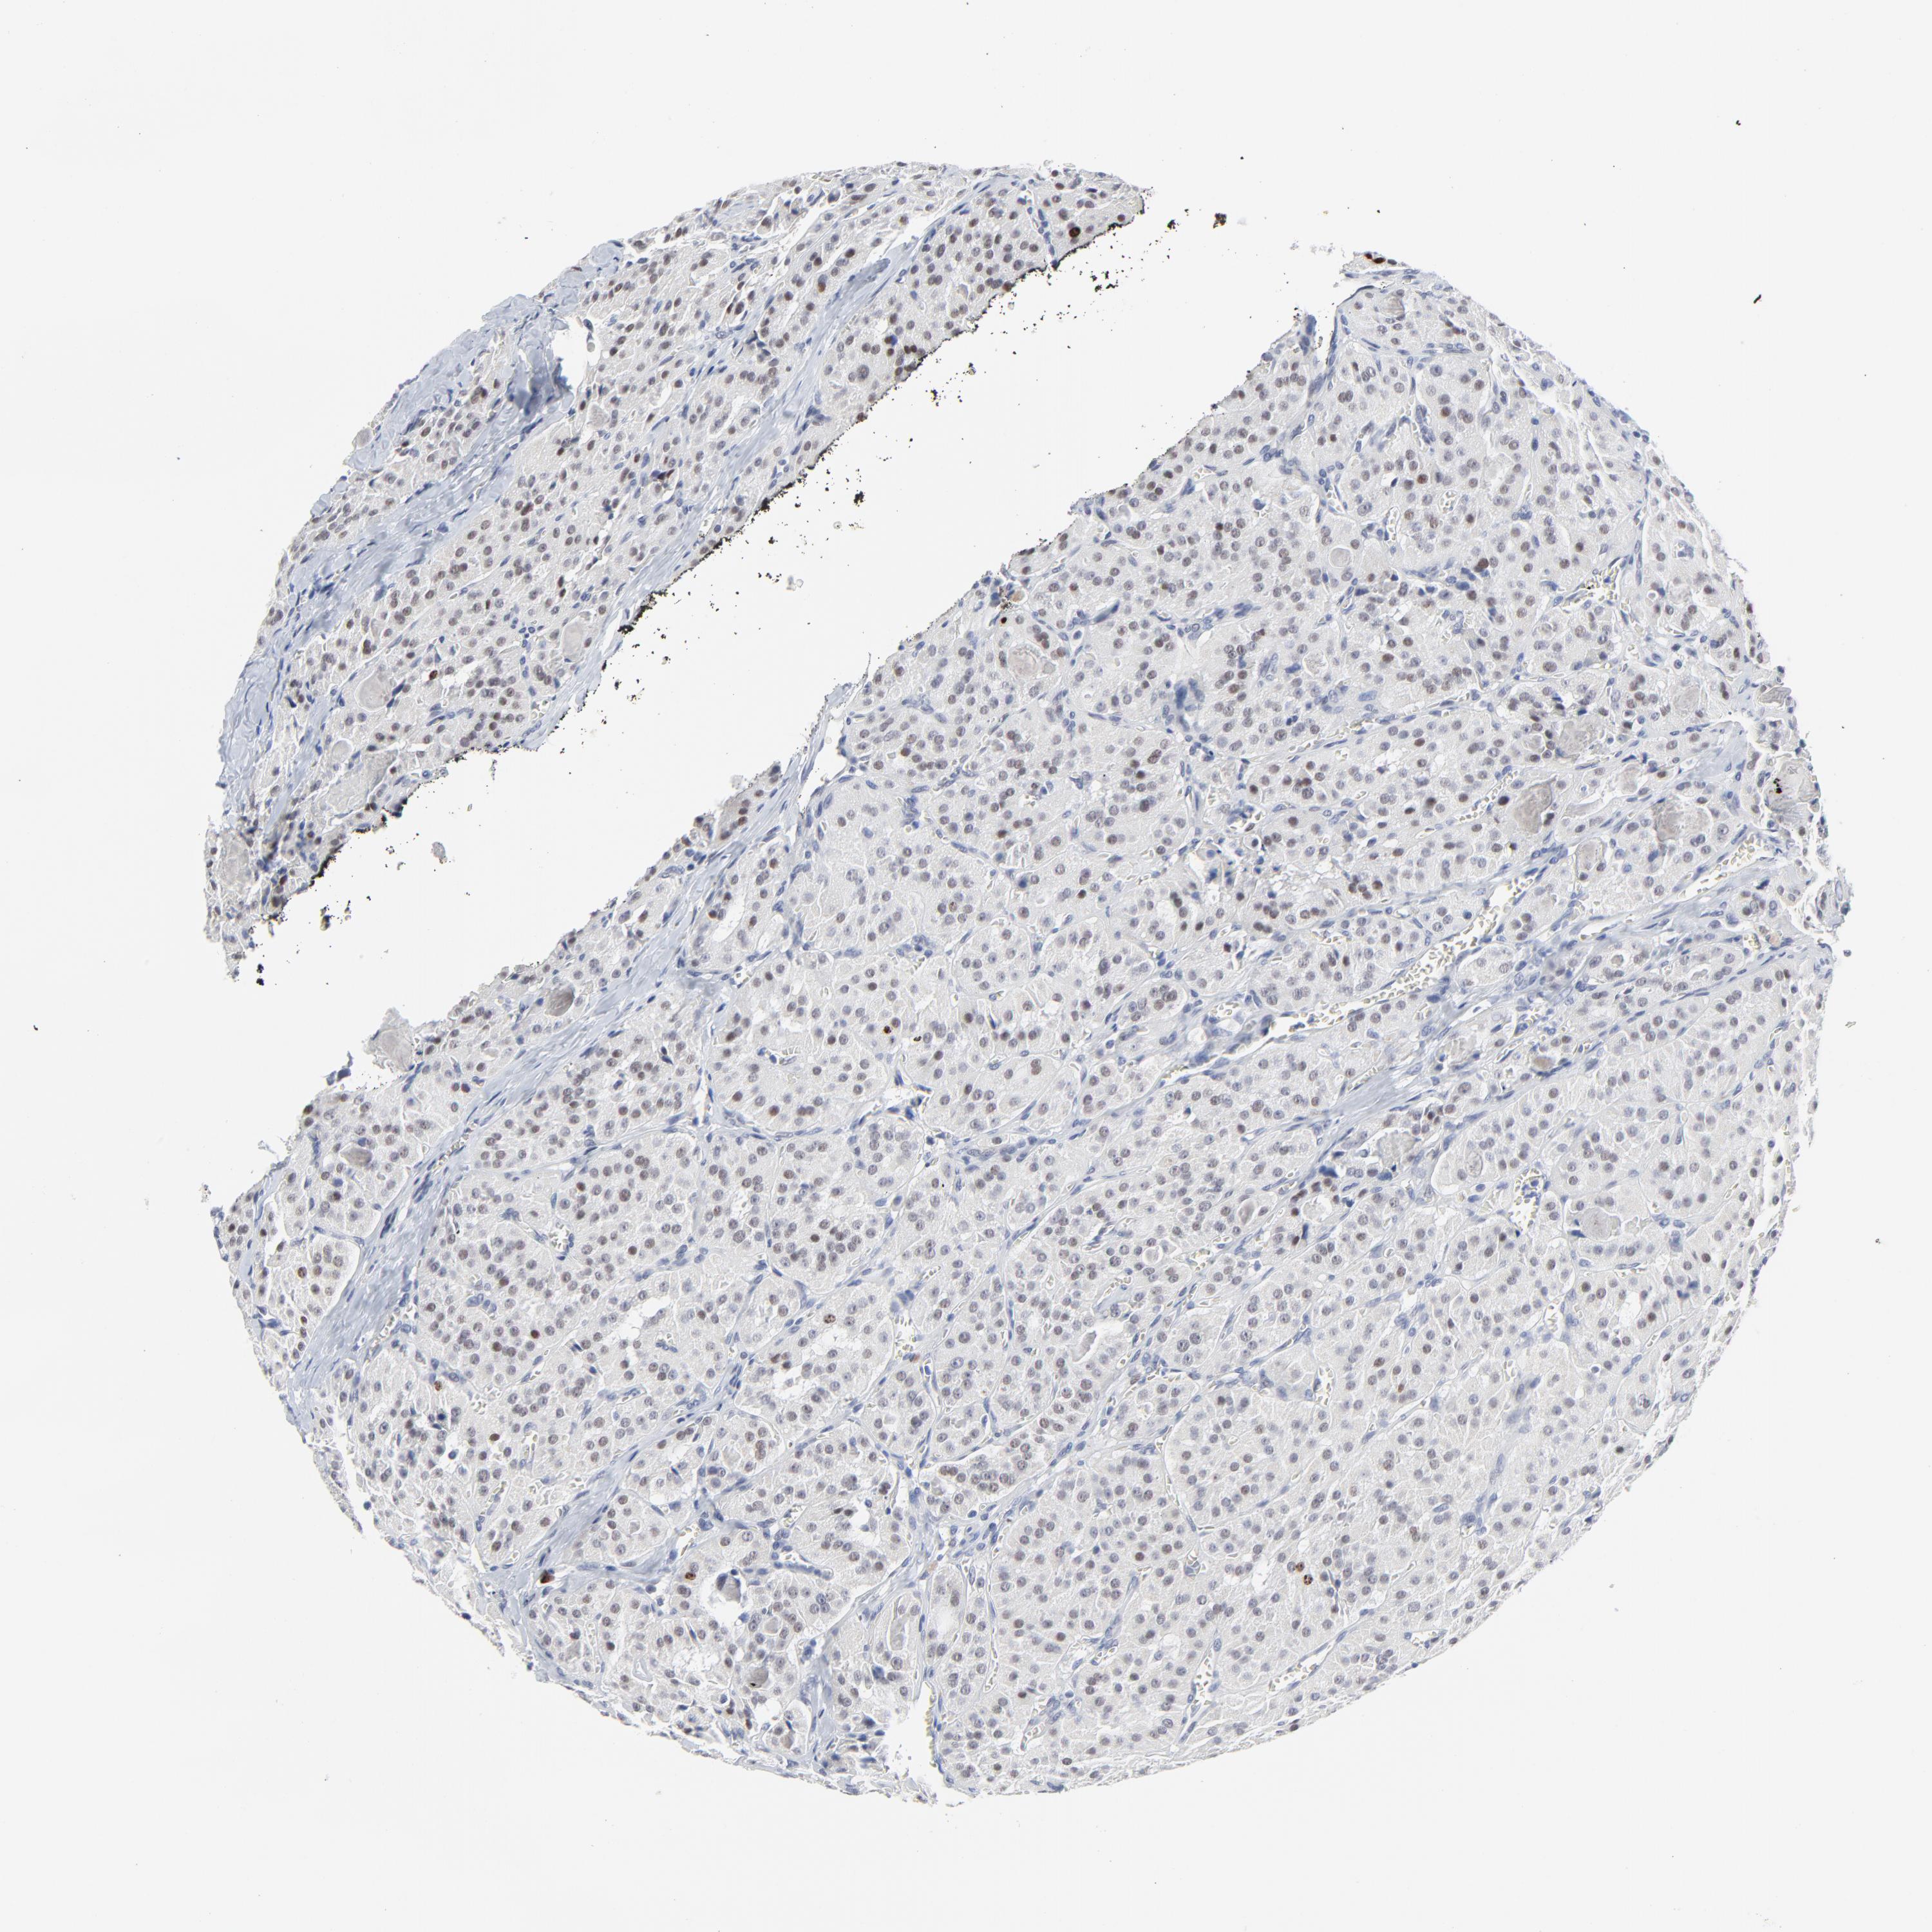

THYROID CANCER - Protein expressioni

A mouse-over function shows sample information and annotation data. Click on an image to view it in a full screen mode. Samples can be filtered based on level of antibody staining by selecting one or several of the following categories: high, medium, low and not detected. The assay and annotation is described here.

Note that samples used for immunohistochemistry by the Human Protein Atlas do not correspond to samples in the TCGA dataset.

Antibody stainingi

Antibody staining in the annotated cell types in the current human tissue is reported as not detected, low, medium, or high, based on conventional immunohistochemistry profiling in selected tissues. This score is based on the combination of the staining intensity and fraction of stained cells.

Each image is clickable and will lead to virtual microscopy that enables deeper exploration of all samples and also displays staining intensity scores, fraction scores and subcellular localization as well as patient and tissue information for each sample.

Antibody HPA003145

Staining

High

Medium

Low

Not detected

Intensity

Strong

Moderate

Weak

Negative

Quantity

>75%

75%-25%

<25%

None

Location

Nuclear

Cytoplasmic/membranous

Cytoplasmic/membranous,nuclear

Carcinoma, NOS

Follicular adenoma carcinoma, NOS

Papillary adenocarcinoma, NOS